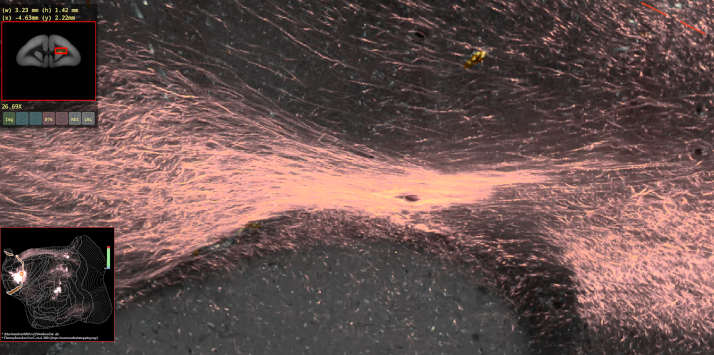

高解像度の脳画像を、手軽にウェブブラウザ上で表示できるようにするため、JavaScript を使って高解像度画像ビューアを自作しました。初めての JavaScript で、正直スパゲッティコードだらけですが(笑)、意外とちゃんと動いています。ぜひ画像をクリックして、コモンマーモセット脳画像の美しさをご覧ください!